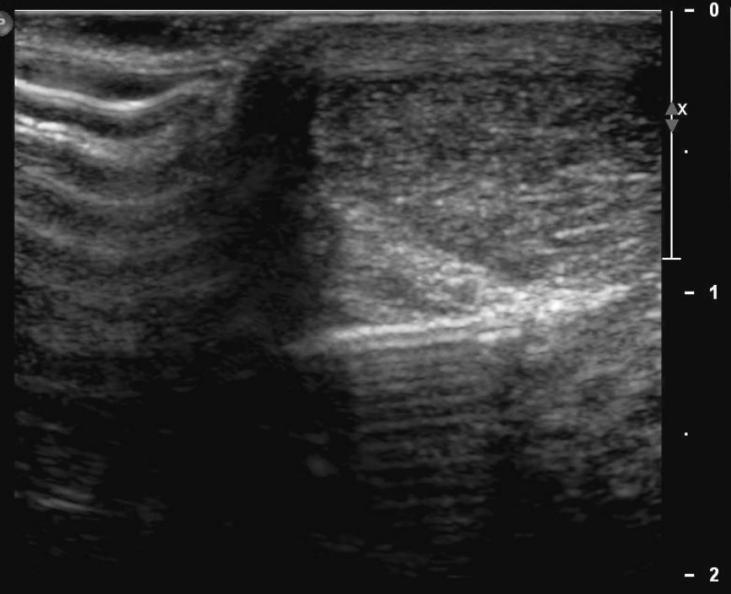

Ce traitement consiste en l’injection d’un volume important de NaCl 0,9% en péritendineux (40 ml), après avoir effectué une anesthésie locale de 5ml de Bupivacaïne 0,5%.

Fig.1 Aiguille en contact avec le tendon achille

Fig.2 Remplissage du péritendon de 40 ml de NaCl 0.9%

Après l’injection, le mollet est bandé et un repos de 48 heures est nécessaire. Dès le 3ème jour, un traitement de physiothérapie est initié. Un traitement antioxydant per os (1 gr de vit.C / j.) pendant 2 mois est prescrit après l'infiltration.